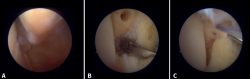

Técnica quirúrgica: tratamiento artroscópico de las lesiones agudas de la sindesmosis

La técnica se realizará utilizando los portales anteromedial y anterolateral convencionales. El portal anteromedial se emplea para la visualización, mientras que el portal anterolateral sirve como portal de trabajo. Una vez visualizado el espacio tibioperoneo, resecaremos la sinovial inflamada con un shaver artroscópico para facilitar la reducción (Figura 7A). Posteriormente, mediante visión directa restauraremos el espacio tibioperoneo, teniendo muy en cuenta la posible malrotación del peroné, especialmente en fracturas de tipo Maisonneuve. Para la reducción peronea utilizamos una pinza de tipo Verbrugge que nos permite corregir la rotación. En nuestra experiencia, una vez limpiado el espacio y si la posición es correcta, es poco frecuente tener que utilizar una pinza compresora entre tibia y peroné.

Figura 7. A: desbridamiento del espacio tibioperoneo; B: estabilización de la sindesmosis mediante sistema de suspensión.